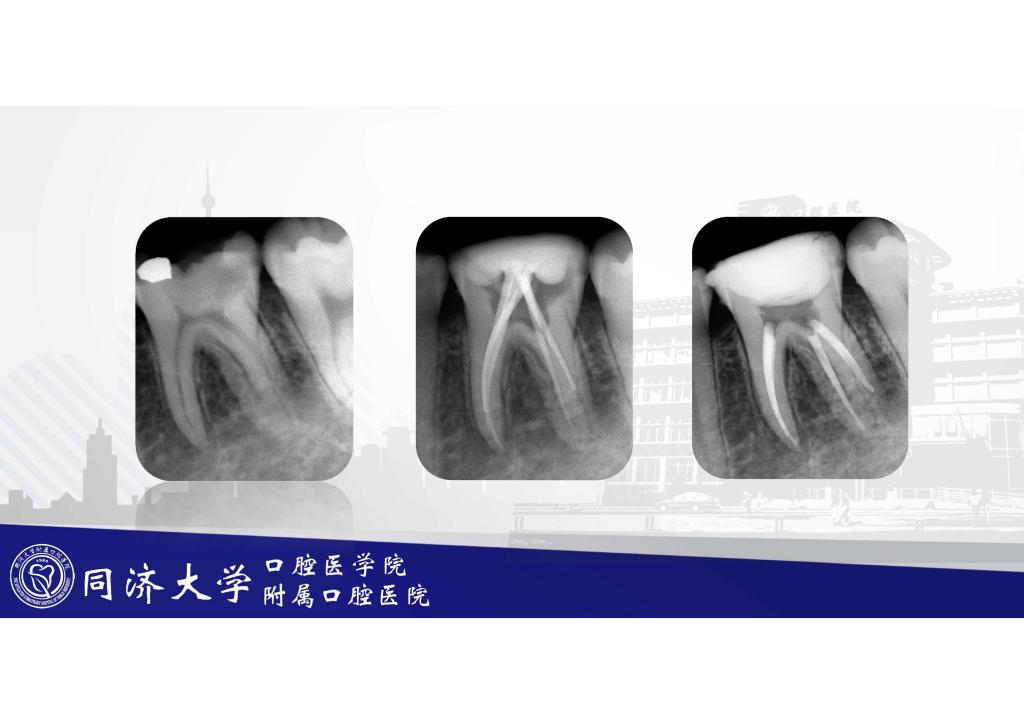

根管治疗之后要做牙套吗?